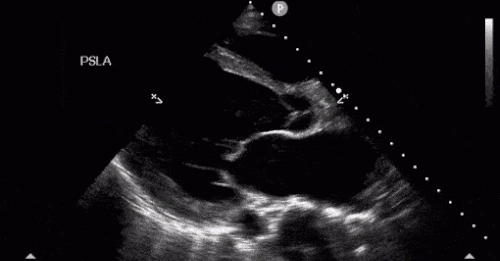

54 Yaş Göğüs Ağrısı Erkek Hasta

Hasta Bilgisi

Yaş / Cinsiyet: 58 yaşında erkekBaşvuru Nedeni: Ani başlayan göğüs ağrısı

Birincil Değerlendirme

Bilinç: Açık, koopere

Solunum: Hafif dispneik, solunum sayısı 22/dk

Dolaşım: Soğuk,...